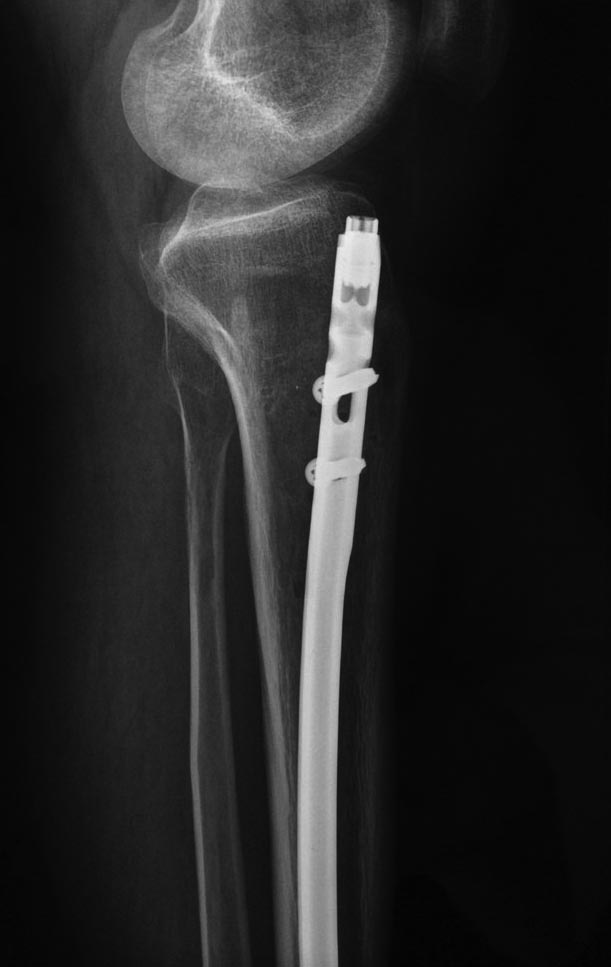

Уважаемые коллеги выразите Ваше мнение по следующему случаю.Молодой человек, 27 лет, находится на лечении с диагнозом: Ложный сустав большеберцовой кости в нижней трети, фиксированный интрамедуллярным блокированным стержнем (12.02.2014 г), ложный сустав малоберцовой кости в нижней трети левой голени, посттравматический артроз левого голеностопного сустава 1 стадии. Укорочение левой нижней конечности на 1,0 см. Со слов пациента известно, что в детстве получил перелом большеберцовой кости, лечился консервативно, перелом сросся с деформацией. Травма в июле 2010 г. бытовая-упал на лестнице, получил перелом малоберцовой кости, и перелом большеберцовой кости без смещения. Выполнена операция: Остеотомия большеберцовой кости в нижней трети, интрамедуллярный блокированный остеосинтез большеберцовой кости левой голени. Гладкое течение послеоперационного периода. Перелом большеберцовой кости сросся. Функция конечности восстановилась. В июне 2013 г выполнена операция удаление интрамедуллярного стержня из большеберцовой кости левой голени. Гладкое течение послеоперационного периода. Приступил к занятием физкультурой, бег. В августе 2013 г спрыгнул с автобуса, с чемоданом в руках, появилась резкая боль в левой голени. За медицинской помощью обратился через 7 дней, при обследовании выявлено: Рефрактура большеберцовой кости. Рекомендовано консервативное лечение в гипсовой повязке. В январе 2014 г. установлен диагноз: Ложный сустав большеберцовой кости в нижней трети, малоберцовой кости в нижней трети левой голени. Контрактура сгибательно - разгибательная левого голеностопного сустава. Посттравматический артроз левого голеностопного сустава 1 стадии. Укорочение левой нижней конечности на 1,0 см. В феврале 2014 г выполнил первым этапом: Фиксацию ложного сустава в АНФ с восстановлением осей сегментов. Через семь дней БИОС с рассверливанием. После операции - вальгус голеностопного сустава. Гладкое течение послеоперационного периода. Нагрузка по переносимости боли. Через 6 недель динамизация, через 2 недели стали мигрировать 2 фронтальных винта. Пытался подкрутить, пришлось удалить. Через 6 мес., контроль - линия ложного сустава прослеживается, но имеется периостальная костная мозоль. Не хватает стабильности.Вопрос что делать?Вариант № 1- выполнить реостеосинтез с рассверливанием КМК и на 12 мм диаметра гвоздь (стоит 11 мм)и убрать ротацию стопы руками одномоментно или одномоментно при помощи АНФ во время операции. Вариант № 2 выполнить удаление гвоздя, сделать все то же, что 6 месяцев назад, но с восстановлением анатомических взаимоотношений в голеностопном суставе.Вариант № 3 Двухэтапно, вторым этапом пластина на большеберцовую кость + костная пластика области не сращения.Вариант № 4 удаление гвоздя и лечение в КДА. Вопросы:1. Какой вариант оперативного лечения будет оптимальным в данном случае.2. При двухэтапной методике в дистальном отломке имеется канал от гвоздя, как направить гвоздь к наружному отделу дистального отломка большеберцовой кости. Есть опасения, что гвоздик может пойти по тому же каналу. Использовать поллер спицы или винты – сработают ли? И достаточна ли будет жесткость фиксации дистального отломка большеберцовой кости на гвоздике при 3 – 4 винтах при реостеосинтезе гвоздем.3. Нужен ли остеосинтез малоберцовой кости в нижней трети, с целью создания латеральной опоры. К сообществу за советом.

Возможно, не все снимки выставлены, потому что не нашел признаков проведенной динамизации, о которой писали. Верхние винты остались нетронутыми, трудно опознать динамизацию. По поводу применения “cap” на гвозде имеется сомнение, потому что высоко расположенный по верхнему краю гвоздь не позволяет воспроизвести динамизацию. Перед динамизацией надо укорачивать гвоздь или убирать “кап”.